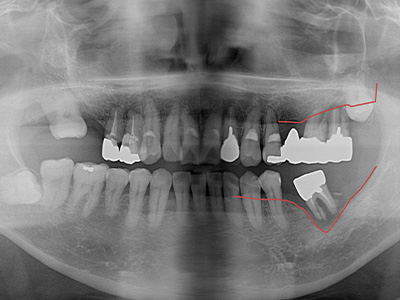

「補綴主導型インプラント」

一切妥協しないインプラント

最終的な被せ物(補綴)の理想的な形・位置から逆算し、インプラントを噛み心地と見た目に最適な位置に設計・埋入します。

技工士と院長が共同で設計し、その中心に正確にインプラントを配置。自然な見た目と快適な噛み心地の両立が可能になります。